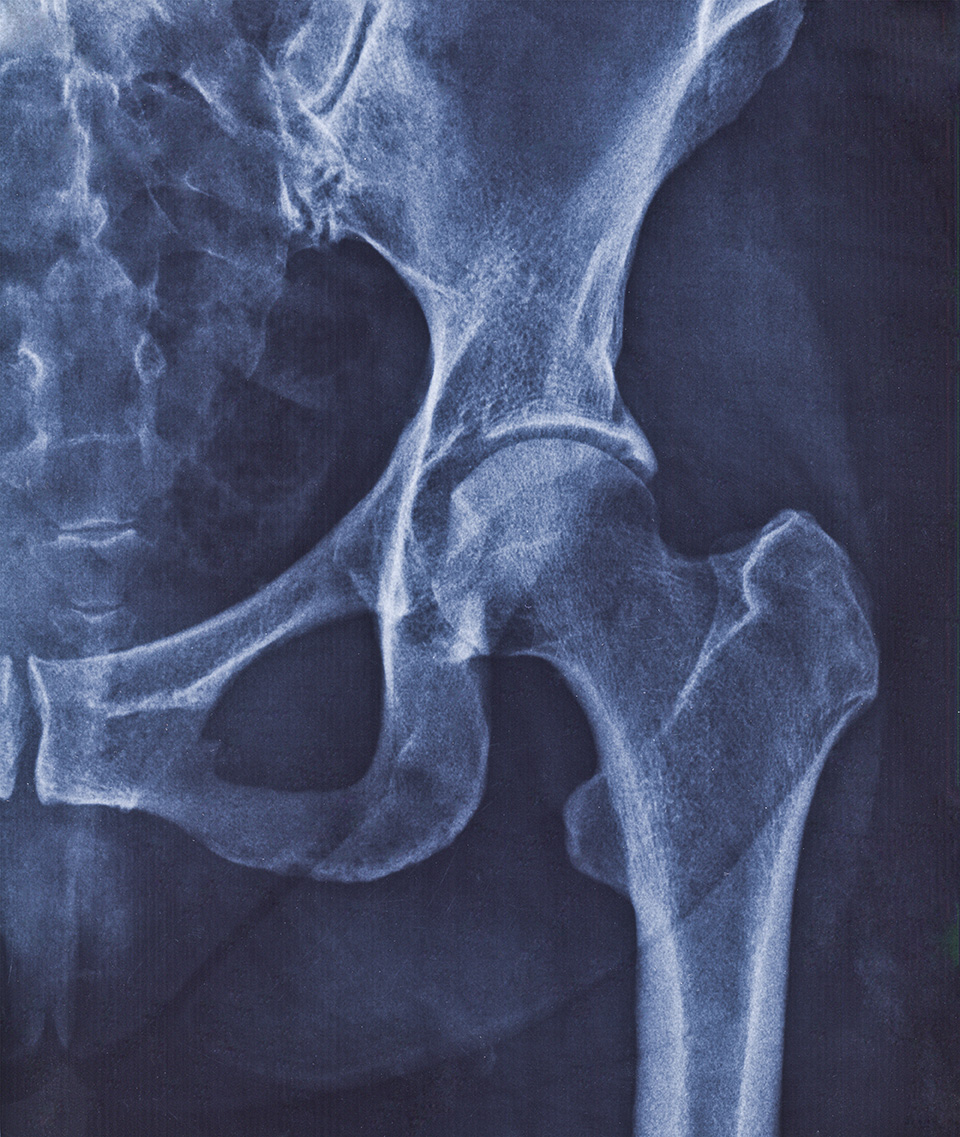

Understanding Your Hip Anatomy

The specialists at Orthopaedic Hospital of Wisconsin provide the latest in surgical and rehabilitation interventions to help eliminate your hip pain and get you moving again. Understanding your hip anatomy helps explain why certain conditions develop and how our treatments work to restore function.

Your hip joint is one of the largest weight-bearing joints in your body, designed for both stability and mobility. The complex interaction between bones, cartilage, ligaments, and muscles enables a wide range of motion necessary for walking, running, and daily activities.

Your hip is a versatile ball-and-socket joint. The ball is formed by the upper end of your femur (thigh bone) and fits into the socket, which is formed by the acetabulum (concave surface of your pelvis). The cartilage that coats the ball and lines the socket provides a smooth gliding surface, allowing your hip joint to move fluidly. Hip pain or limited mobility can result from a range of conditions or injuries, but effective treatment can help you return to your daily activities.